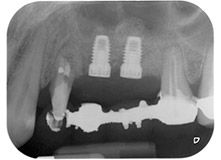

След един месец, в деня на операцията, болката и възпалението в зъб 24 е минимално, но подвижността в Miller class 2 е на лице. След отваряне на ламбата и почистването на периапикалната и перирадикуларната тъкани, обхватът на костния дефект стана очевиден (Фиг. 2 и 3).

В букалния корен, цялата вестибуларна и дистална кост липсва. Захващането е значително ограничено до палатиналния корен, подчертавайки предварително лошата прогноза. Зъб 27 също откри намалено хоризонтално захващане и минимално апикално разреждане (Фиг. 1) без клинични симптоми.